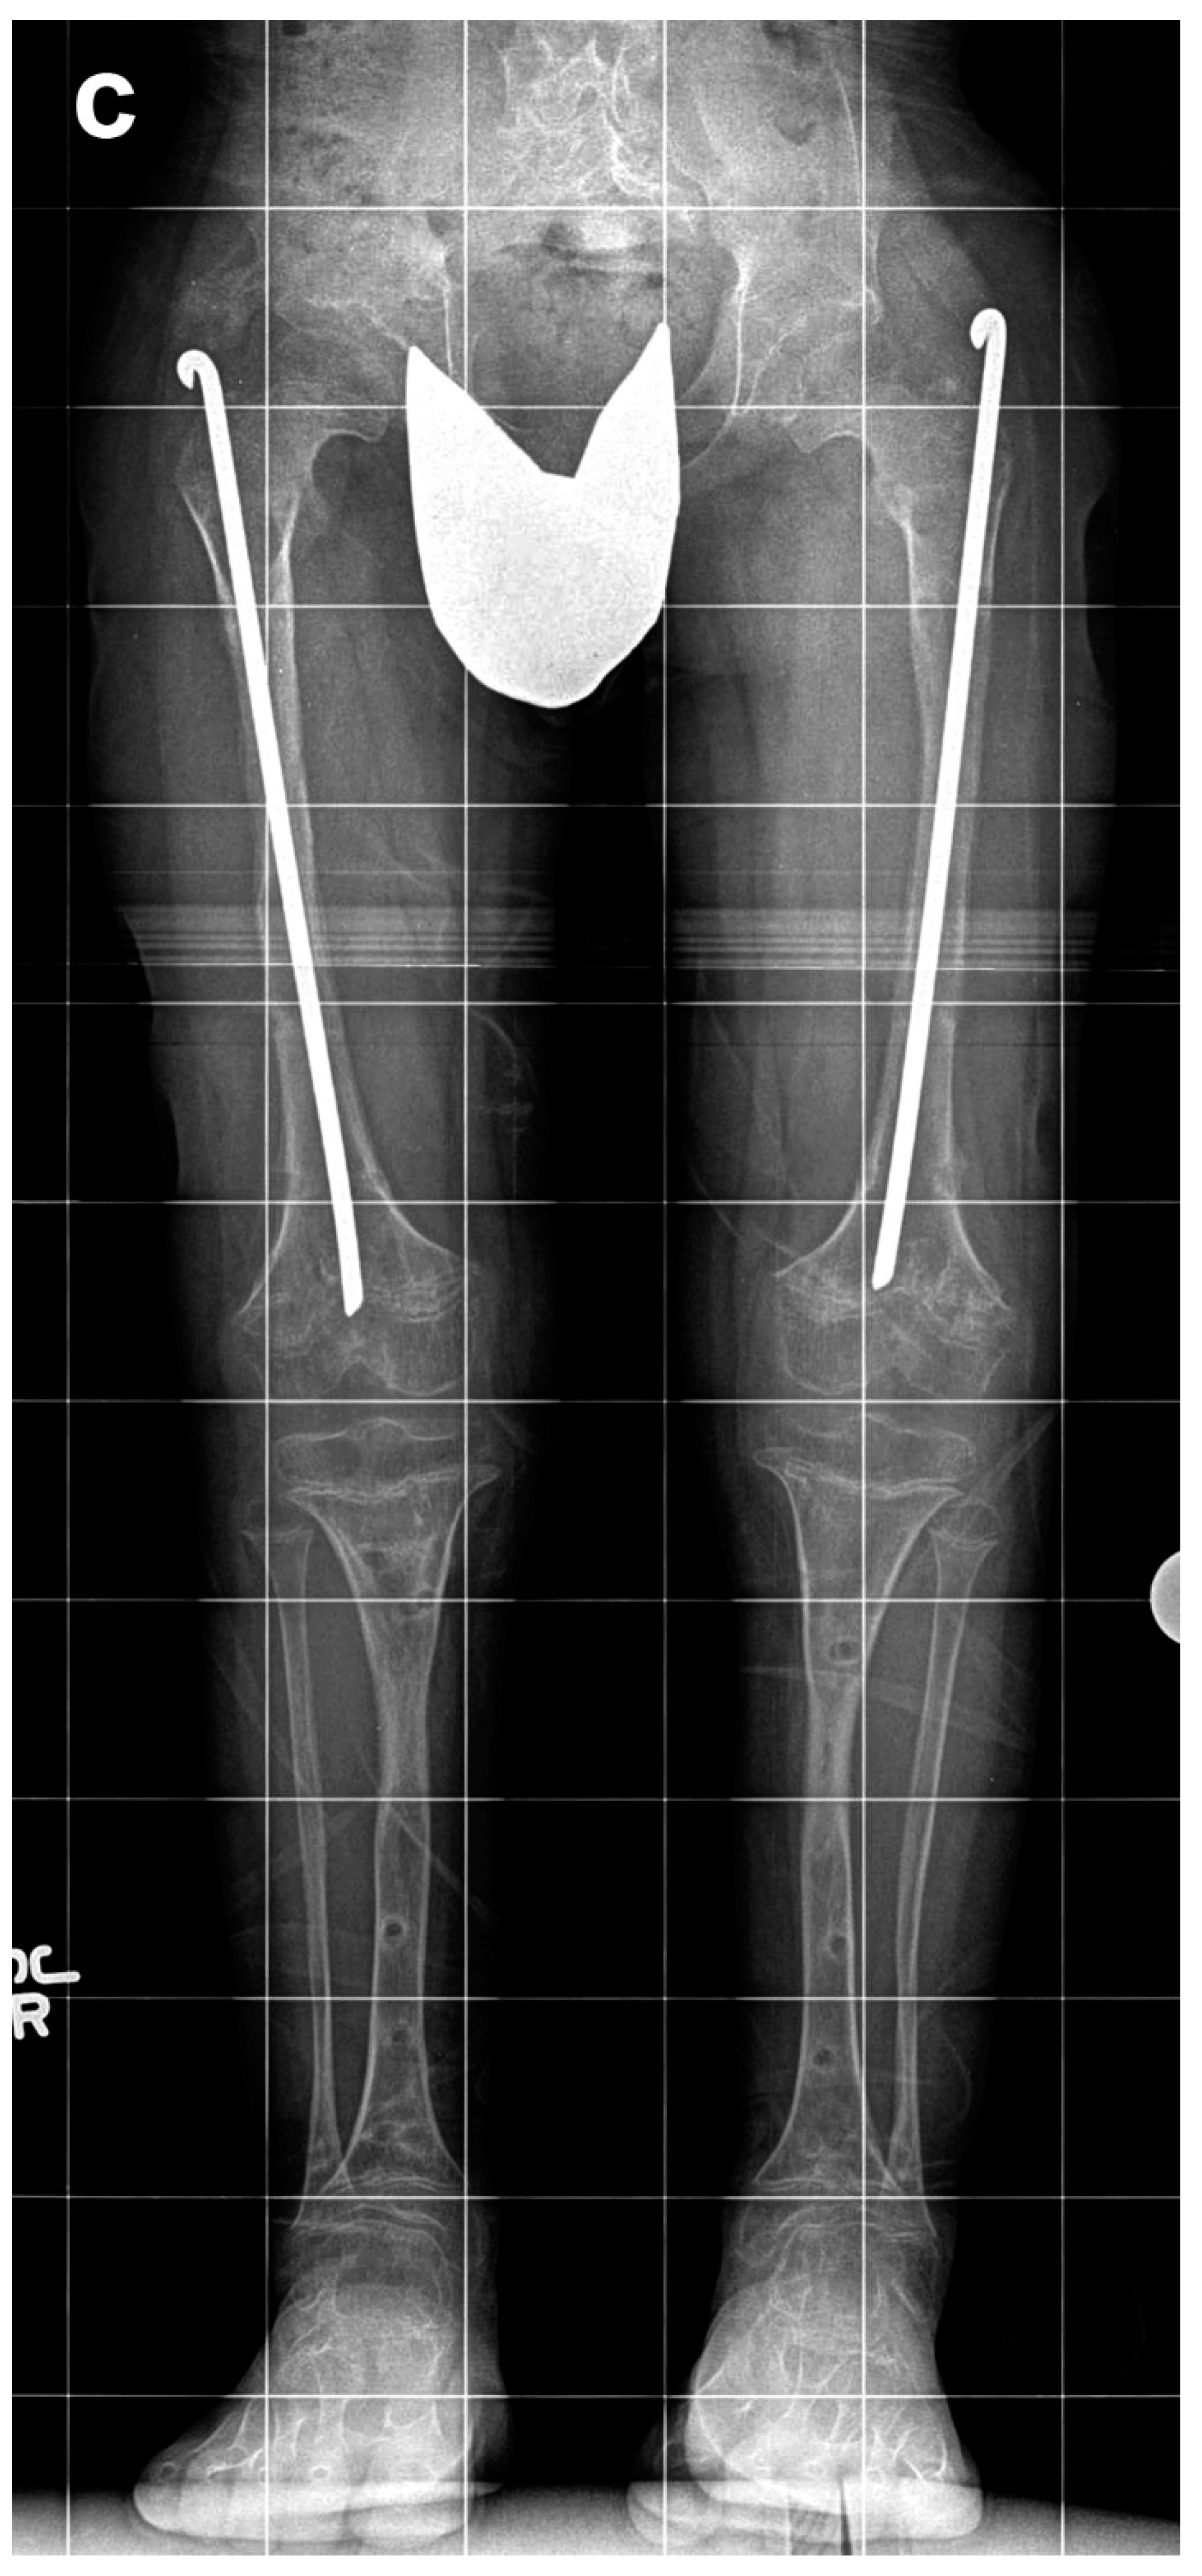

Figure 2. Eight-year-old boy who underwent two simultaneous bilateral femoral tibial lengthening (SBFTL) procedures. A Taylor Spatial Frame (Smith & Nephew, London, UK) was used for the tibia, and an Orthofix LRS (Lewisville, TX) was used for the femur. (a) Prior to first limb lengthening. (b) During first SBFTL. (c) Status after 10-cm lengthening. (d) Prior to second limb lengthening. (e) During second SBFTL. (f) Status after additional 12.5-cm lengthening (used with permission).

Of these 64 patients, nine patients were excluded as they underwent SBFTL using other methods of fixation, such as internal femoral nail or a combination of internal fixation for the femur and external fixation for the tibia. An additional five patients did not have at least 12 months of follow-up after external fixation removal and were excluded from this analysis. Fifty patients (29 males, 21 females, 200 bone segments) with achondroplasia met our inclusion criteria and underwent a total of 65 lengthening procedures (260 bone segments underwent lengthening). We defined a “procedure” as SBFTL (Figure 2).